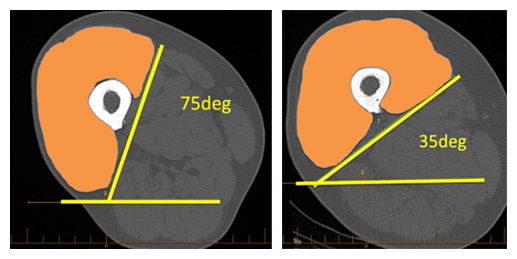

The muscle alignment can be measured directly but this requires thigh scans. A simpler technique is to measure the alignment of the quadriceps tendon relative to the knee joint. Lateralisation of the proximal end of the quadriceps tendon is an indicator of an unbalanced lateral force vector. The techniques are described in detail in the papers above and in the YouTube videos.

It is not just a malalignment of the quadriceps tendon – though measuring the quadriceps tendon alignment is a reliable surrogate for quadriceps muscle deformity. The muscle deformity can best be described by a rotation of the proximal muscle relative to the femoral shaft and knee joint. The range of rotational malalignment is at least 75 degrees. There are clear differences in the relative shape and alignment of the four components in of the quadriceps. It is also not caused by wasting of the vastus medialis components – which was actually 15% larger in patients with laterally rotated quadriceps. This challenges the long-held belief that patella maltracking is caused by weakness of the VMO – instead it appears to be a rotational malalignment of the entire quads.